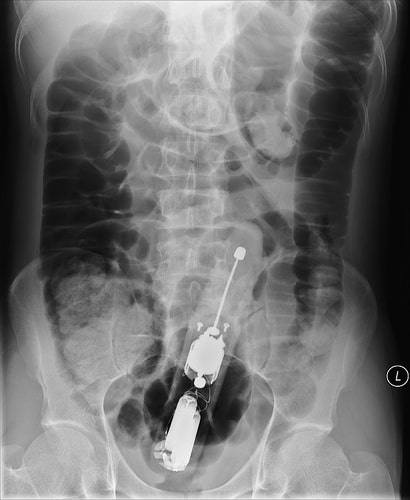

9. Un sextoy

Toujours lire la notice d’utilisation.

sextoy

(source photo : ebaumsworld)